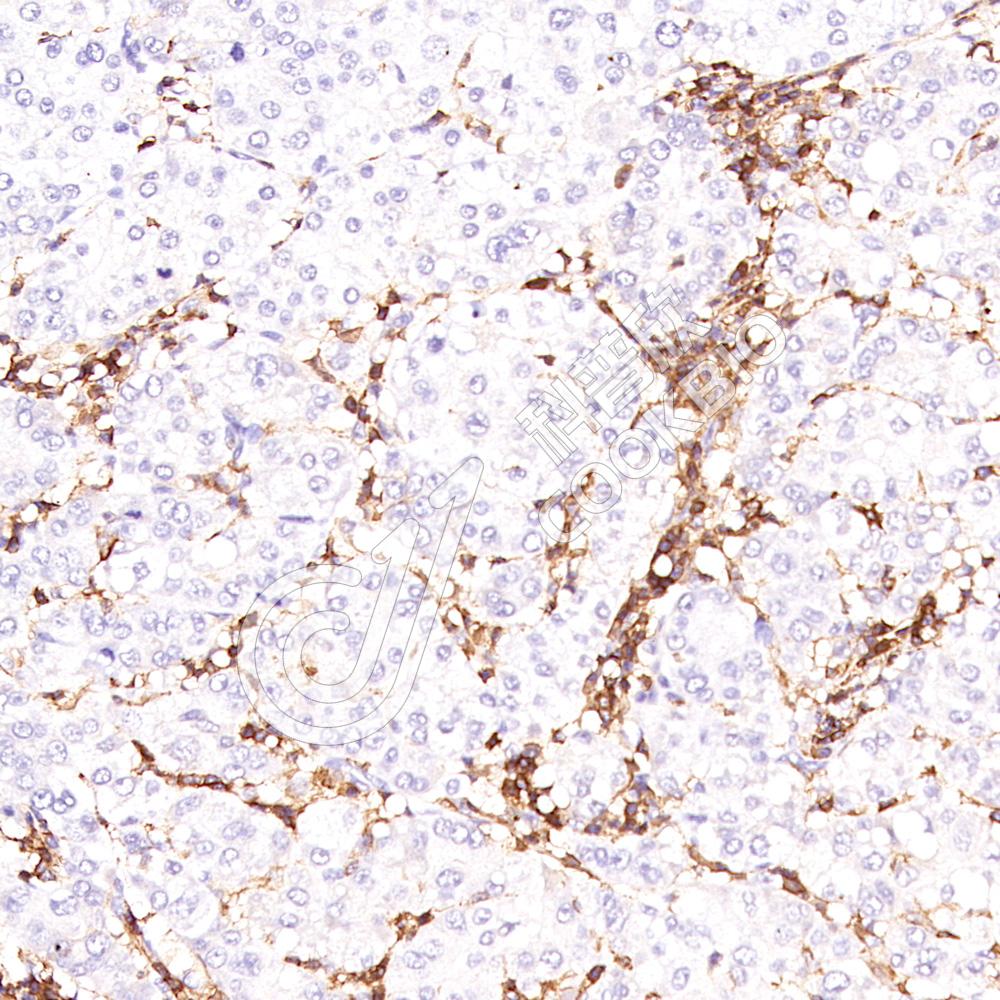

IHC检测CD3蛋白(货号 K1334011).

样品: 人扁桃体, 4%多聚甲醛 (货号KSG1101) 固定12-24小时.

抗原修复: 柠檬酸抗原修复液(干粉, pH 6.0) (KSG1201), 高压锅均匀喷气计时2分钟.

—抗: 1: 1100稀释, 4℃ 孵育过夜.

二抗: S-vision免疫组化多聚二抗(山羊抗兔),即用型 (货号KB3906), 室温孵育20分钟.